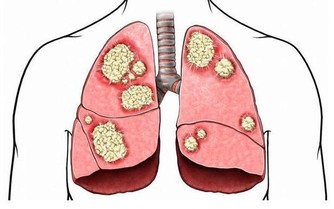

❶ 、【功能主治】養陰清肺,化痰益氣。用於肺熱燥咳、陰虛勞嗽、乾咳痰粘、氣陰不足、煩熱口乾。

❶、【功能主治】養陰潤肺,清心安神。用於陰虛久咳,痰中帶血,虛煩驚悸,失眠多夢,精神恍惚。具有養陰潤肺止咳功效,用於肺陰虛的燥熱咳嗽,痰中帶血,如百花膏。治肺虛久咳,勞嗽咯血,如百合固金湯。具有清心安神功效,用於熱病餘熱未清,虛煩驚悸,失眠多夢等。藥用時煎服,10~30g。清心宜生用,潤肺蜜炙用。 ❷、【功效】養陰清熱,滋補精血。 16玉米須 玉米須味甘、淡,性平;歸腎、肝、膽經;質輕滲降;具有利尿消腫,平肝利膽的功效;主治水腫,小便淋瀝,黃疸,膽囊炎,膽結石,高血壓病,糖尿病,乳汁不通。有利尿降壓功能。 廣告 - 請繼續往下閱讀 17紅豆 ❶、【性能】味甘,性平。能健脾利濕,散血,解毒。 ❷、【用途】用於水腫、腳氣;產後缺乳,腹瀉、黃疸或小便不利;痔瘡,腸癰。 18杏仁

富含蛋白質、脂肪、糖類、胡蘿蔔素、B族維生素、維生素C、維生素P以及鈣、磷、鐵等營養成分。其性苦微溫,有小毒,滋潤養肺通便。適用於陰虛肺熱、咳嗽、咽乾舌燥、大便乾結者。 19羅漢果

廣告 - 請繼續往下閱讀 其性甘涼,清熱潤肺止咳通便。 20紫蘇